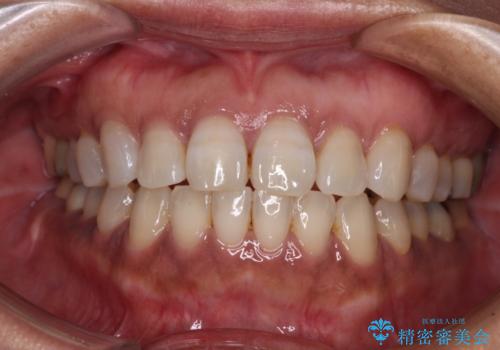

治療前に、いくらインビザライン矯正がオープンバイトを得意としているとは言え、さすがに限界があるだろうと思っておりましたが、前歯でレタスが噛めるまで改善することができました。

顔の印象も大きく変わり、患者様には大変満足していただきました。